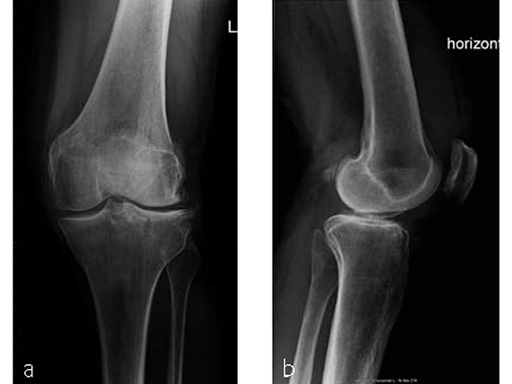

A 70-year-old female patient had an accident while hiking. Osteoporosis was preexisting but with asymptomatic moderate degenerative osteoarthritis of the knee with chondrocalcinosis of the lateral compartment (Fig 1 and 2).